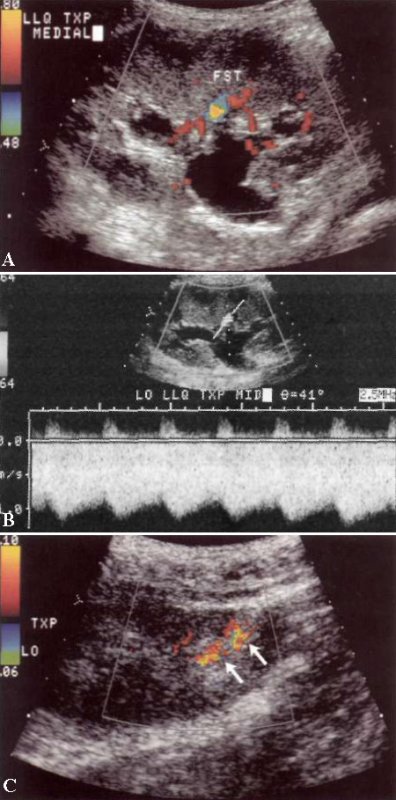

УЗИ: Артериовенозная фистула трансплантата почки

Фото 3. Артериовенозная фистула трансплантата почки. А – цветовая допплерограмма трансплантата почки в поперечной плоскости демонстрирует венозный кровоток высокой скорости (синий), возникающим на фоне других сосудов, которые являются артериями (красный), направленными к почке. В – спектральная допплерограмма демонстрирует венозный кровоток, скорость которого с коррекцией угла составляет 1 м/с. В этом случае нужно обратить внимание на артериальную форму волны в вене, которая немного замедлена по отношению к волне почечной артерии. С – артериовенозная фистула в области нижнего полюса трансплантата почки после проведения процедуры биопсии демонстрирует типичный допплеровский «шум» (разноцветные пиксели), что свидетельствует на турбулентность потока и вибрацию окружающей паренхимы. Реальный размер фистулы гораздо меньше, поэтому на УЗИ в режиме серой шкалы она не визуализировалась. У данного пациента фистула была бессимптомной и закрылась самостоятельно